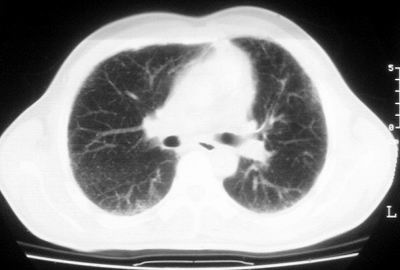

患者,男,44岁,糖尿病4年余,近期消瘦、乏力。化验检查:总胆红素26.33(参考值:5.1-17.2u mol/l),直接胆红素:6.4(参考值:0-4.3u mol/l),谷-丙转氨酶(alt):843(参考值:<40u/l),hbsag(+),抗hbs(-),hbeag(-),抗-hbe(+),抗-hbc(+)。

1\\粟粒性肺结核可能性大,支气管肺泡癌不排除

双肺散在小结节影,考虑粟粒性肺结核.肺窗薄扫会更好看些.

双肺外侧带胸膜下可见网状阴影,考虑轻度肺间质纤维化。

双肺纹理增强并可见网格状影达外带,考虑双肺感染并轻度间质纤维化

1.双肺急性粟粒型肺结核;2.少量腹水.

肺间质纤维化并肺部感染,结合不能排出,毕竟糖尿病人易合并之,建议结合ppd检查或hrct进一步扫描。